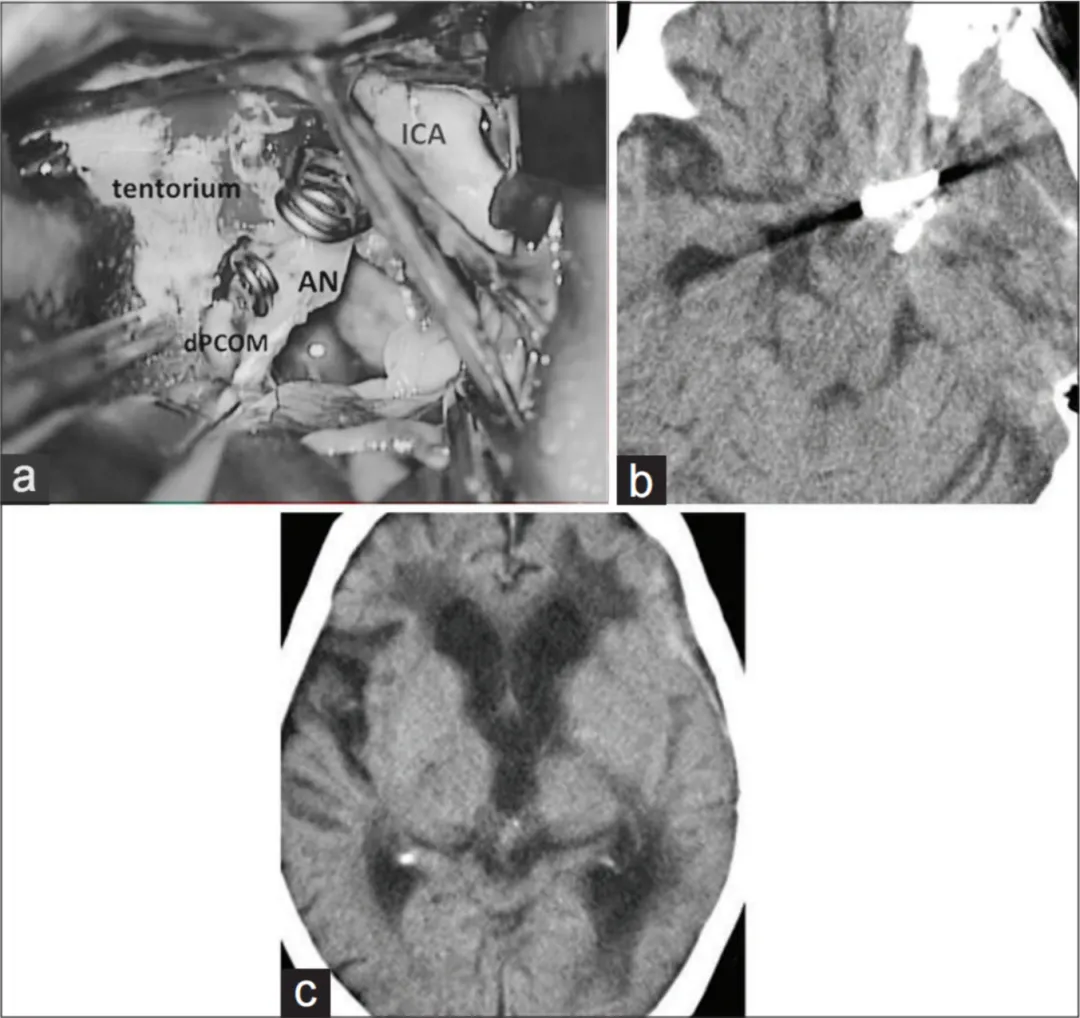

(a)经左侧经外侧裂入路的手术视野:动脉瘤已完成夹闭,瘤顶切开后实施了完整血栓切除术,未发现动脉瘤周围的滋养血管

ICA——颈内动脉(Internal carotid artery);

AN——动脉瘤(Aneurysm);

dPCOM——后交通动脉远端(Distal part of posterior communicating artery))。

(b)、(c)术后计算机断层扫描(CT)显示,脑干受压解除,且无缺血性病灶。